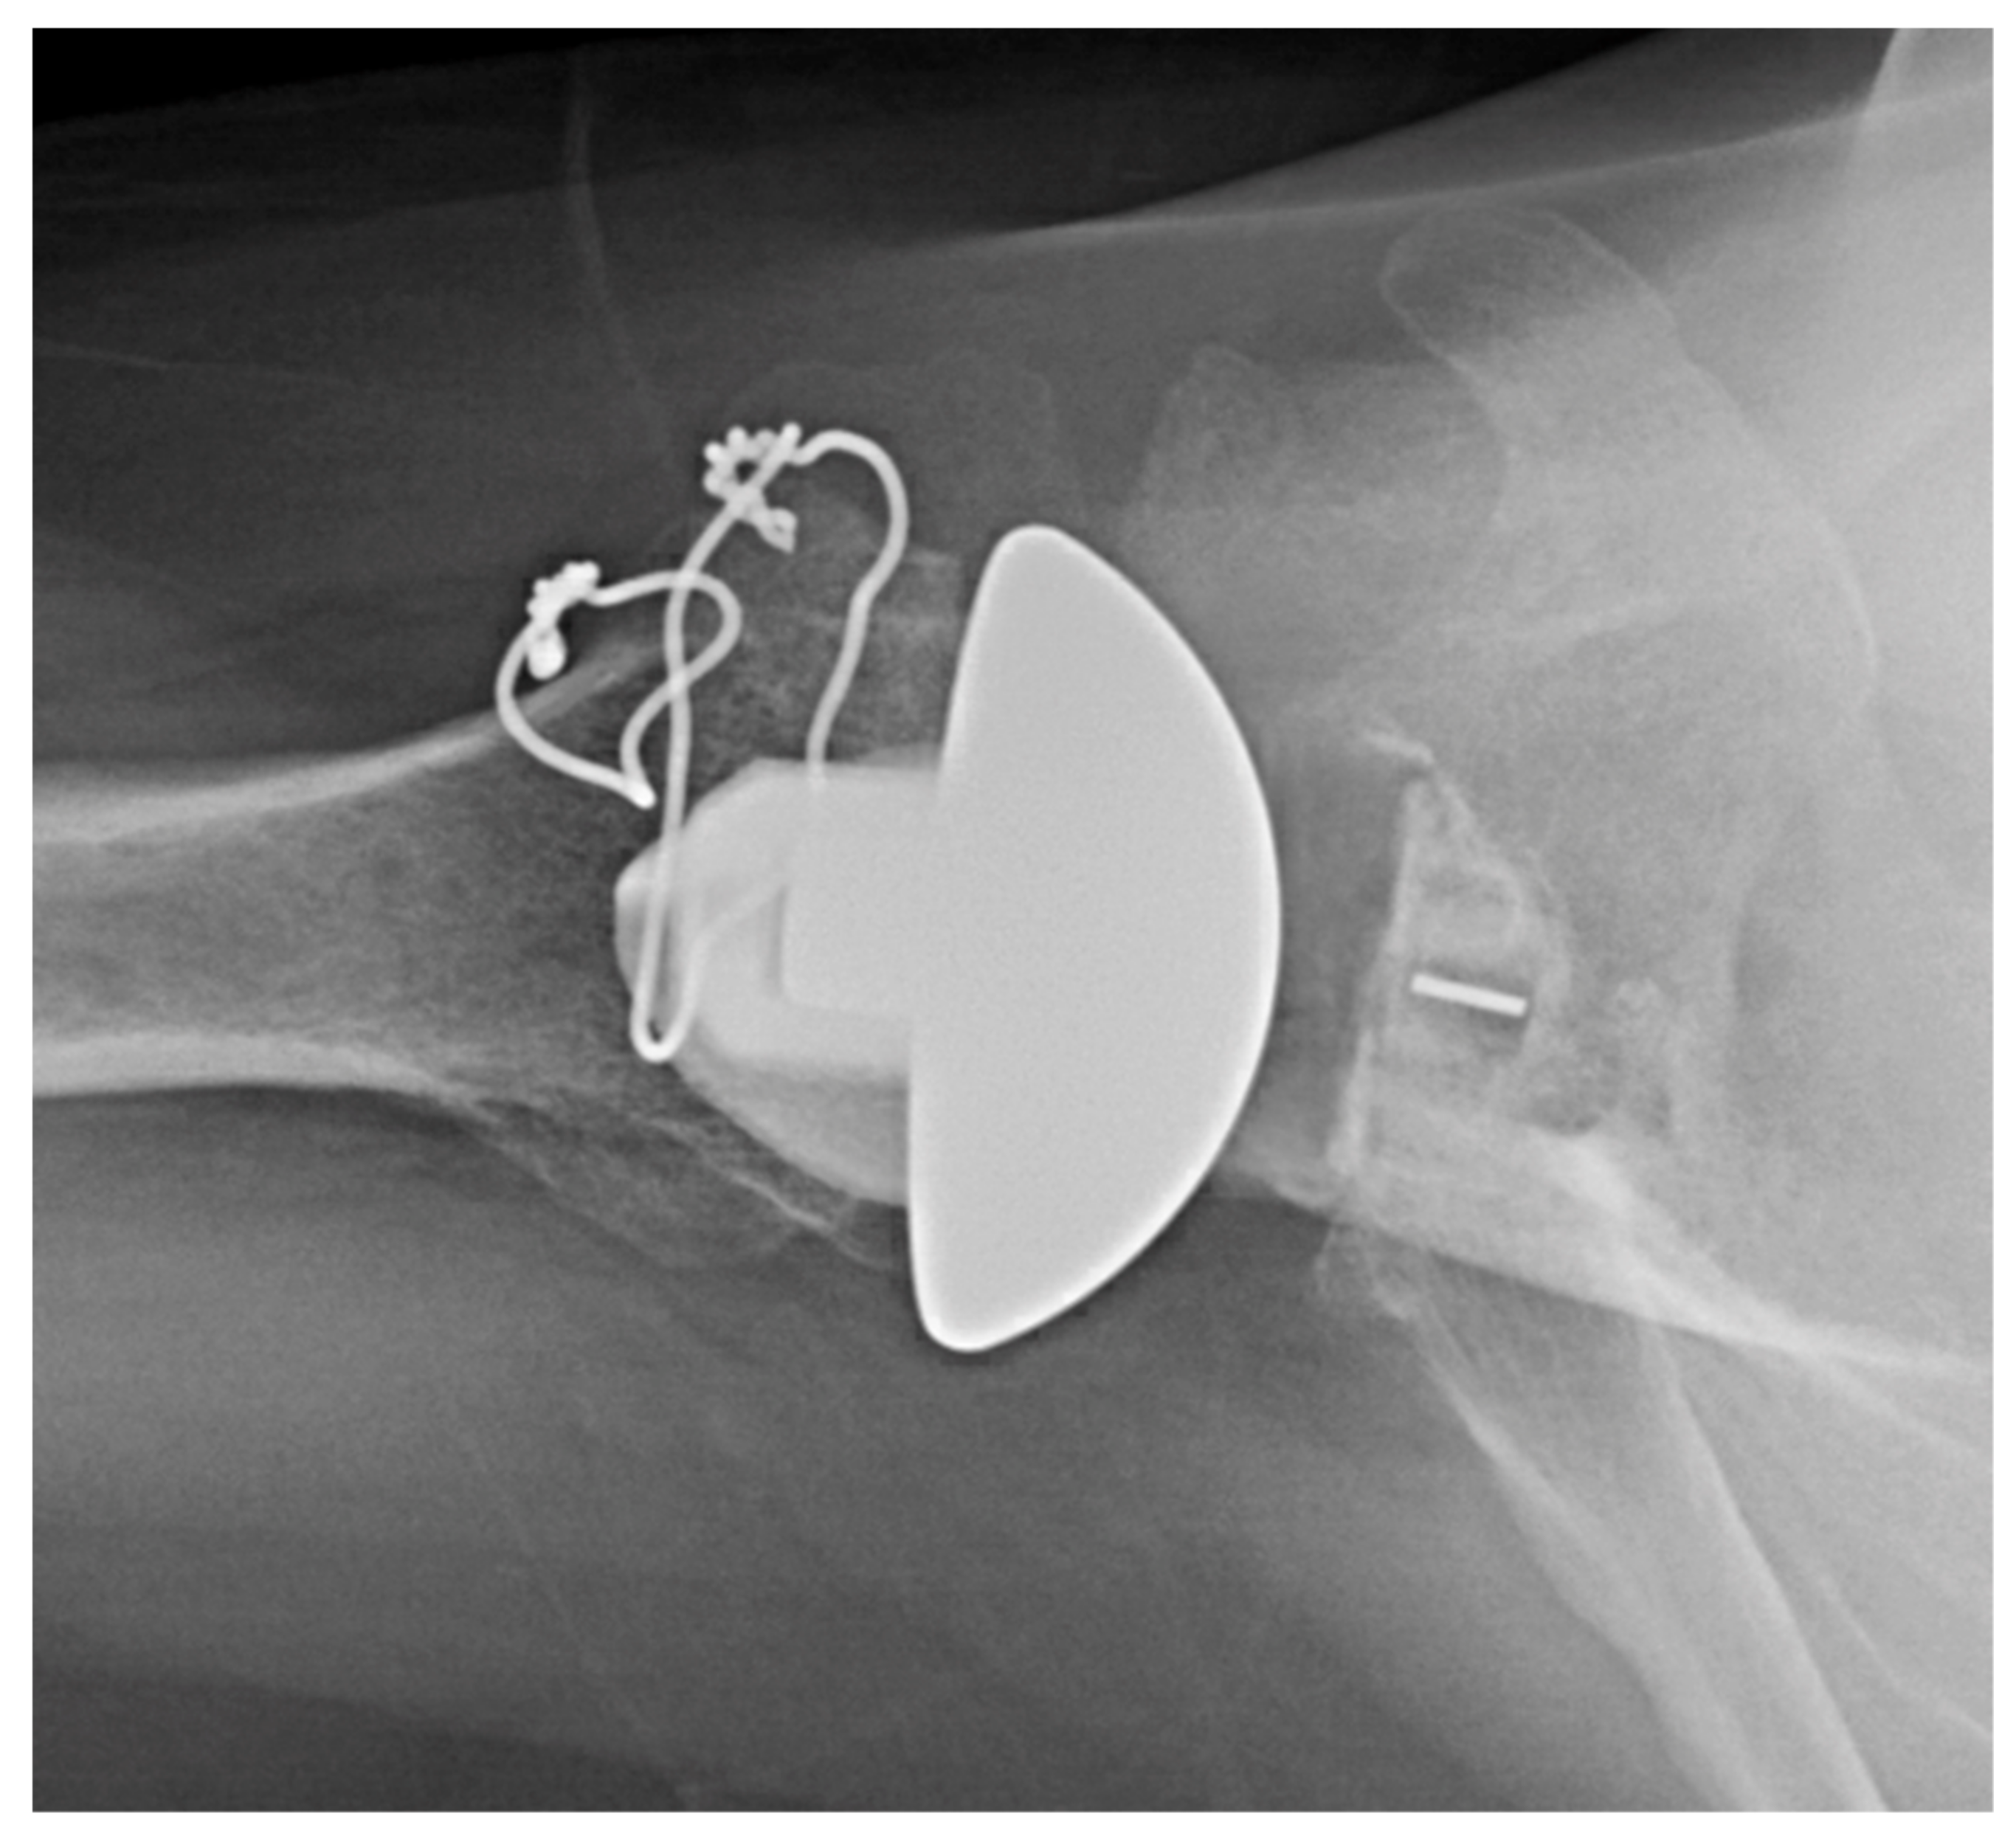

2.1.1. Stemless Implants

3.2.2. Inlay vs. Onlay Implants